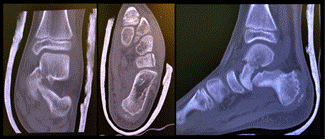

Inicialmente se solicitaron radiografías y tomografía axial computada que mostraron una luxofractura de cuello de astrágalo con desplazamiento del cuello medialmente asociado a una fractura del cuboides.

La fractura de astrágalo de nuestro paciente fue clasificada según Hawkins como una tipo 2.

Se destaca la asociación de una fractura del hueso cuboides la cual fue clasificada como tipo simple AO y tipo 3 de Fenton y Nammari (fractura intraarticular).

Fig. 2 Tomografía axial computada, cortes coronal axial y sagital. Fractura de cuello de astrágalo, desplazamiento medial. Corte axial, fractura cuboides.